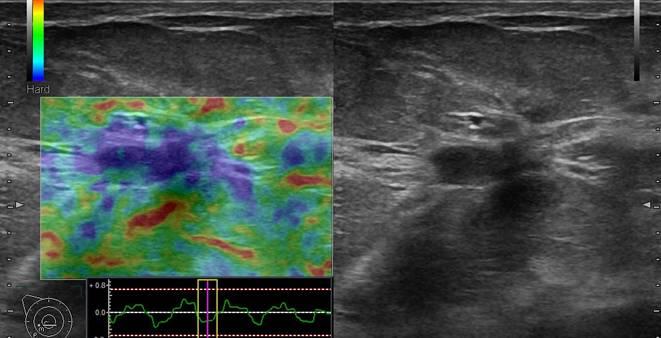

Ung thư vú

» Thông tin: Nữ giới – 50 tuổi.

» Lâm sàng: Khối tuyến vú.